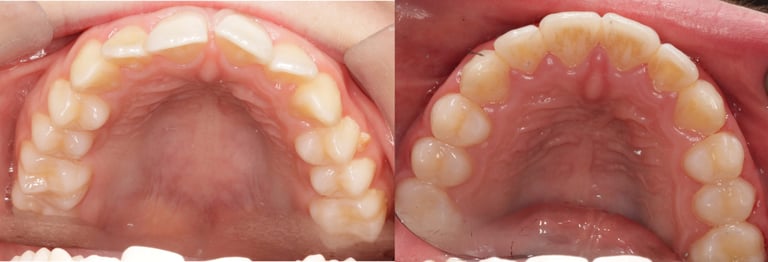

Fixed case 1

This teenage patient didn't quite qualify for NHS treatment had fixed braces with me on a private basis. After approximately 9 months, the fixed braces were removed and fixed retainers placed.